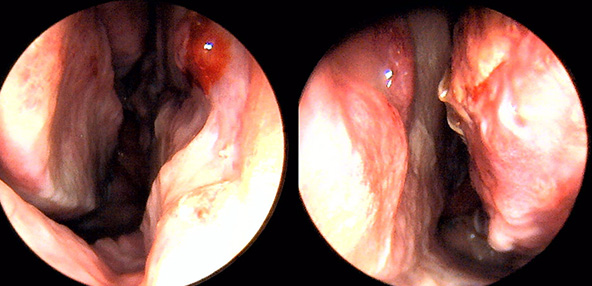

※ 비중격 비염 수술 후 생길 수 있는 부작용으로는 출혈, 감염, 염증이 있을 수 있습니다.

본 사진은 의료기관에서 진료를 본 환자이고, 전후 사진 인물이 동일인이며,동일조건에서 촬영이 되었습니다.